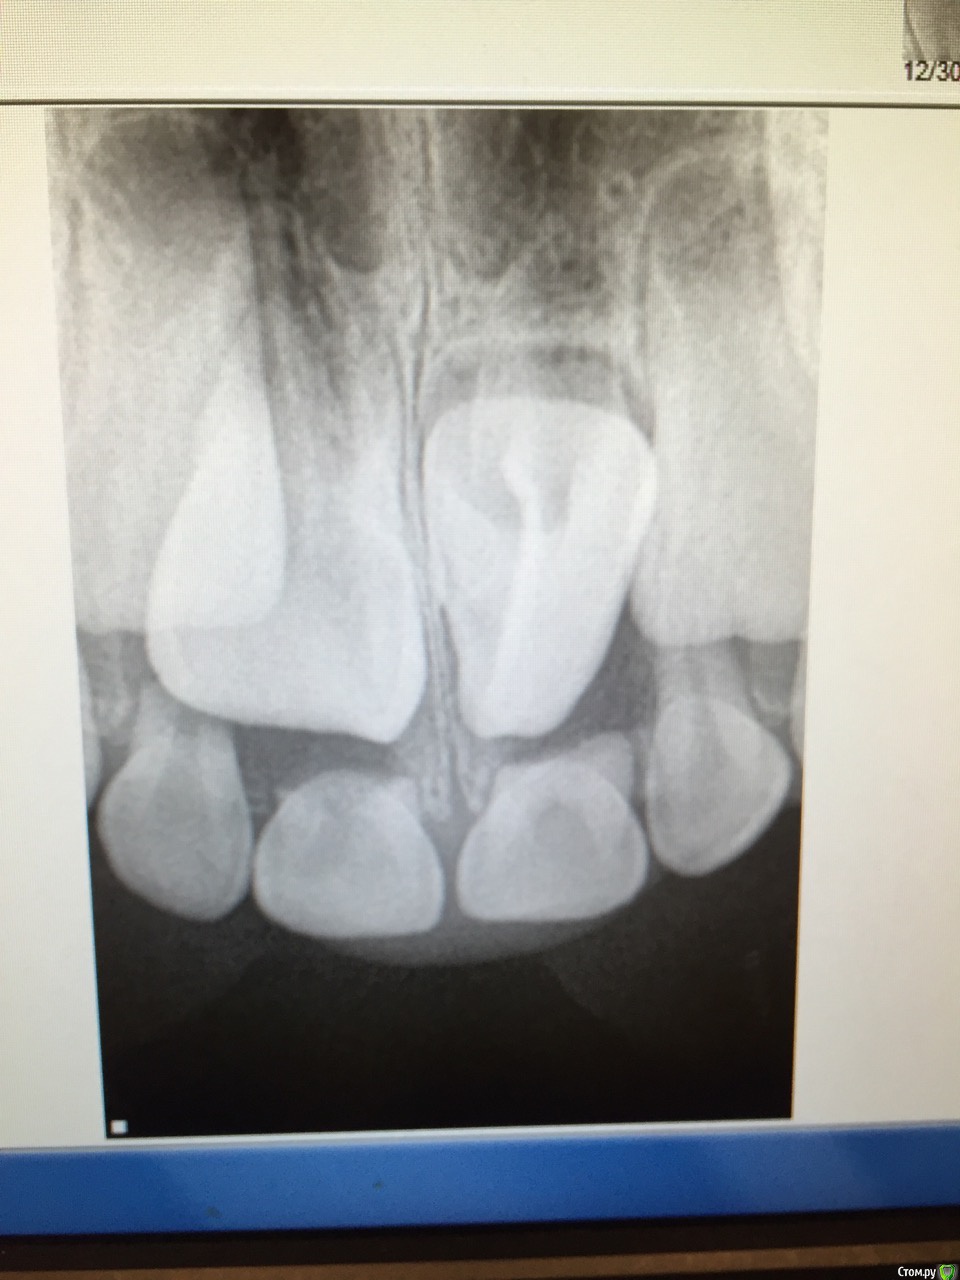

natry Опубликовано 5 января, 2016 Поделиться Опубликовано 5 января, 2016 Уважаемые коллеги, не подскажите что делать в данном случае. Девочка 6 лет пришла просто для осмотра, без жалоб. Родители отрицают какую нибудь травму в прошлом. Куда отправить в начале, орто или хирург? Ссылка на комментарий

Джима Опубликовано 5 января, 2016 Поделиться Опубликовано 5 января, 2016 (изменено) круто! по виду - обычный резец, такой же, как сосед, только развёрнут и растёт в нёбо. к ортам, думаю, пронаблюдают до прорезывания, разобщат и выставят на место. Главное, не упустить этот момент.а, ну и кт не помешает, да. Изменено 5 января, 2016 пользователем Джима Ссылка на комментарий

natry Опубликовано 5 января, 2016 Автор Поделиться Опубликовано 5 января, 2016 круто! по виду - обычный резец, такой же, как сосед, только развёрнут и растёт в нёбо. к ортам, думаю, пронаблюдают до прорезывания, разобщат и выставят на место. Главное, не упустить этот момент.а, ну и кт не помешает, да.Спасибо. Отправлю для консультации, посмотрим что орто скажут Ссылка на комментарий